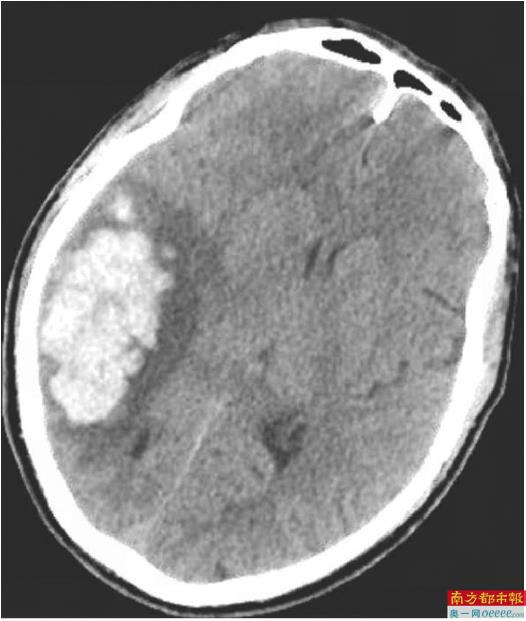

患者术前影像。 通讯员供图

南科大医院神经外科主任鲁春鹤介绍,患者当时右侧顶枕颞叶脑出血量高达约40mL,右侧大脑半球脑水肿、大脑镰下疝接踵而至,生命体征急速恶化,大脑里破裂的血管如同随时可能引爆的“定时炸弹”,情况岌岌可危。